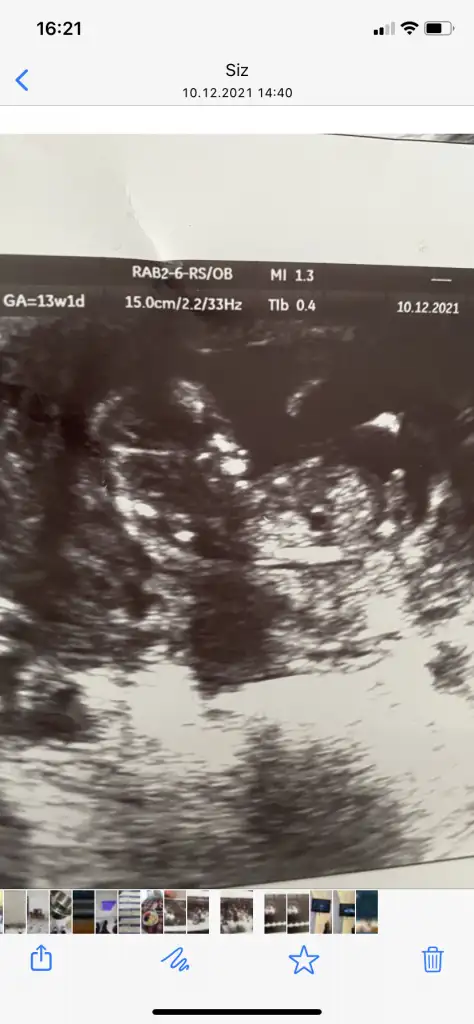

Evet o yüzden Ramzi de vajinalle karın tersi yorum yapıyoruzBu arada kızlar sağda solda falan diyoruz ama dün ne oldu biliyor musunuz?

Doktor bana hep vajinal bakıyordu ya, bu sefer karından göründü.

Vajinal ve karından görüntüler tam tersi oluyo. Vajinalde bebeğin kafası solda, karından sağda görünüyordu.

Doktor karından baktığı için, galiba diğerlerine uysun diye bi tuşa bastı ve görüntü vajinal gibi ters döndü.